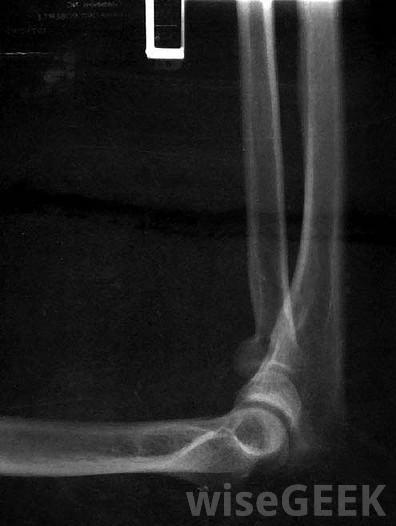

肘部是肱骨、尺骨和桡骨这三块骨头连接在一起的地方。你的肘部必须允许你的手臂上下运动,同时也要让你的手臂翻转过来。任何一块或多块肘部骨折都会导致肘部骨折。为了治疗肘部骨折,你必须首先医生。如果骨头需要复位、移动或调整,他或她会帮你做。可能需要进行x光检查以确定肘部损伤的严重程度当你肘部骨折后去看医生,医生会给你做检查。在检查过程中,你可能要拍X光片,回答关于你受伤的问题以及受伤的原因,让医生测试你的手臂能移动多远。骨头完全断裂可能只需要夹板和休息。如果骨头严重受损或脱离正常位置,或者需要取出骨头碎片,手术可能是一个合适的治疗选择,医生会给你开什么样的治疗方案取决于你的年龄,你受到的损伤的类型,以及骨折后骨骼的位置肘部骨折固定后通常采用物理疗法。除儿童外,通常不使用石膏治疗肘部骨折即使是儿童,骨折的最初几天也通常用夹板治疗。夹板就像石膏一样,只是它不能完全包裹住手臂。夹板通常是用石膏制成的,可以让手臂保持静止,这样骨头可以自行愈合。手臂愈合后,患者可能需要接受康复治疗才能恢复手臂的力量。肘关节。应该肘部骨折包括开放性骨折或神经或血管需要修复时,医生可能会选择手术治疗。有时,这种骨折需要使用针、螺钉或钢板,为了使手臂能够正常愈合。针通常用于儿童,在骨头愈合后可以取出。螺钉和钢板通常用于较大的儿童和成人,如果有不适,可以通过手术移除在愈合过程中,骨骼保持静止是很重要的。结果是手臂在数周或数月内不动。在这种情况下,物理疗法或康复治疗可用于帮助患者恢复手臂的活动。康复包括使用不同的运动,以帮助患者尽可能恢复以前的运动量。医生应告诉您应进行哪种类型的运动以及何时可以进行这些运动肘部骨折通常用夹板和吊索进行治疗,但有时也会使用石膏。